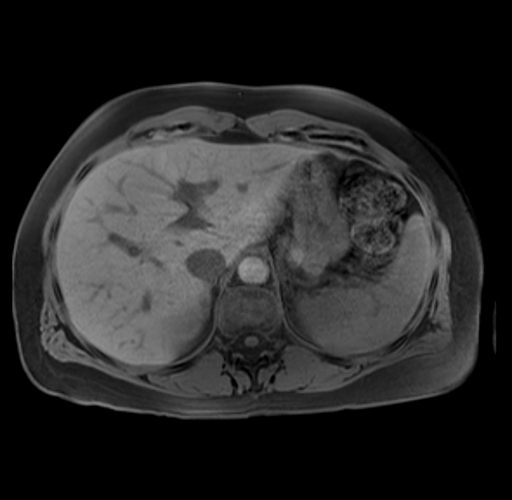

Imaging Analysis

Look through the patient's CT scan to identify any areas of concern for the necessary procedure.

Based on your CT findings, which issue(s) are present and would give reason for "planned slowing down moment(s)" in this case?